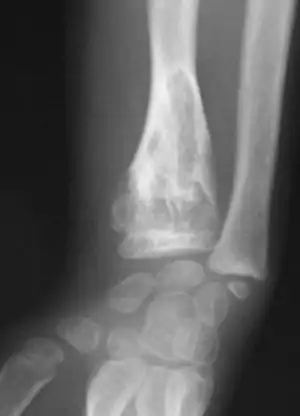

X-ray showing calcified enchondromas localized in finger a 37-year-old patient affected with Ollier disease

X-ray showing enchondromas localized in the lower part of the radius of a 37-year-old patient affected with Ollier disease